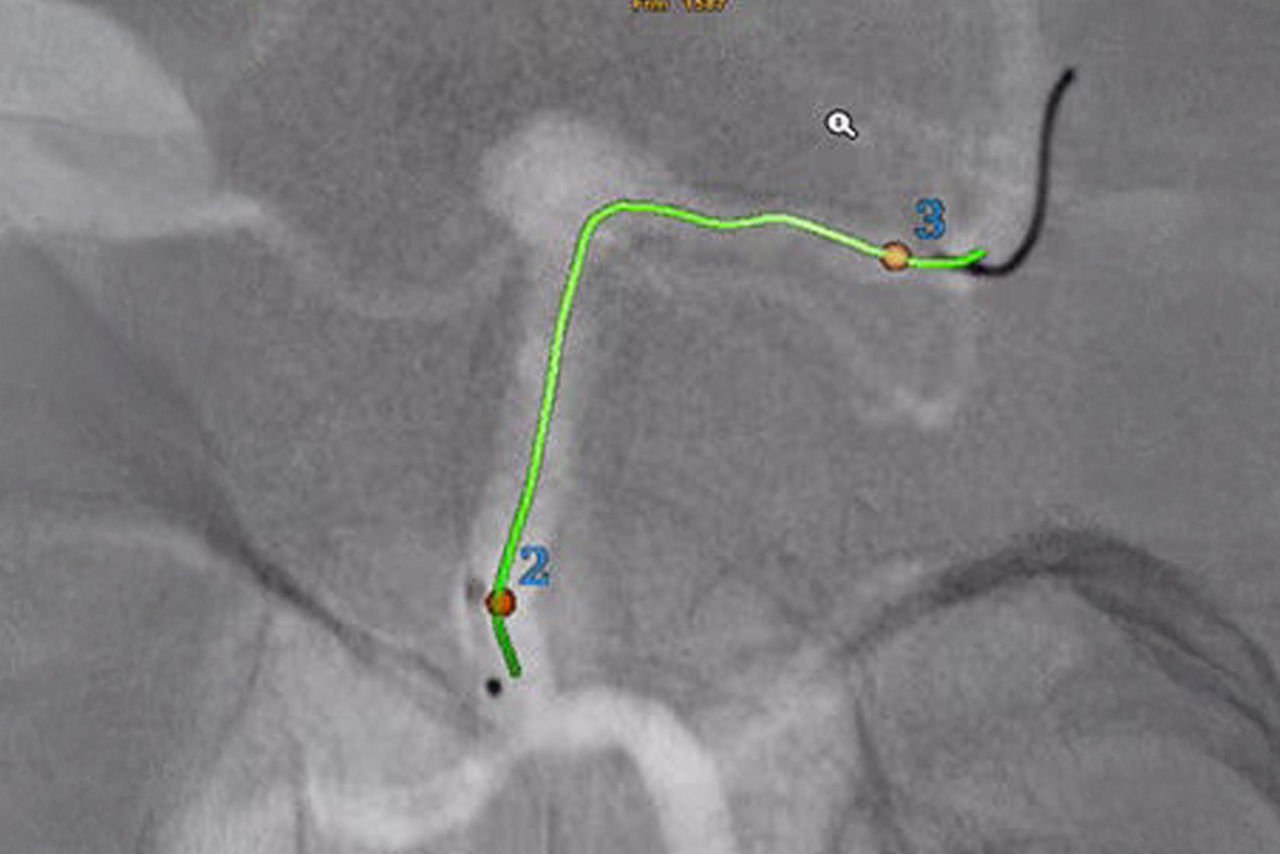

Vessel assist for neurointerventional

Vessel ASSIST delivers accurate and easy anatomy segmentation and accurate vessel quantification from 3D volumes. It also offers advanced 3D roadmap and augmented image guidance capabilities on frontal or lateral planes to guide catheter with confidence for procedure such as Aneurysm Treatment with Flow Diverter.

Segment and size the anatomy of interest in CBCT.1 Plan the stent positioning on the 3D model and prepare 3D landmarks to help guide the deployment.

Import segmented anatomy, centerline and landmarks and overlay them on live fluoroscopy on the frontal or lateral plane for 3D fusion guidance.